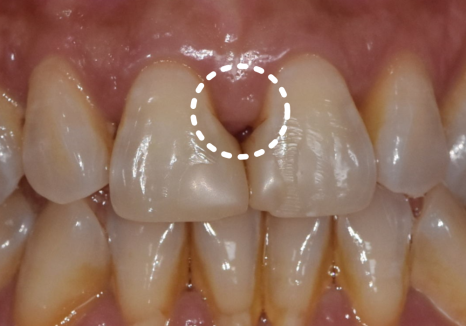

잇몸이 내려가면서 치아 사이 공간이

삼각형 모양으로 검게 보이는 현상을

"블랙 트라이앵글(Black triangle)"이라고 합니다.

실제로 1년 전 초진 사진과

최근 사진을 비교해 보니,

잇몸 퇴축이 눈에 띄게 진행되면서

블랙 트라이앵글의 크기가

이전보다 확연히 커진 상태였습니다.

240716 / 250318

이로 인해

음식물이 반복적으로 끼고,

양치가 점점 어려워지면서

식사 후 불쾌감이 계속될 수밖에 없었던 것이죠.